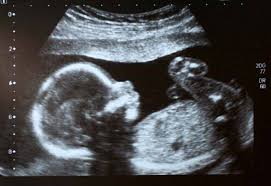

يمكن لاختبارات الفحص أن تساعد على معرفة ما ادا كان الجنين سيولد و هو طفل مع متلازمة داون. فحص الدم واختبار الموجات فوق الصوتية خلال الثلث الأول من الحمل. يظهر فحص بزل السلى للجنين الحامل لمتلازمة داون وجود 47 صبغي، بدلا من 46. بما ان اجراء هذا الفحص يستوجب إدخال إبرة داخل كيس السائل (الأمنيوسي) . عمر الأم، حيث إن تقدم عمر المرأة يزيد من خطر تقسيم الكروموسومات عند الحمل على نحو غير صحيح. وتمثل ال 3 حالات السابقة اسباب الطفل المنغولي الشائعة و النادرة. الحمل والولادة بشكل عام هو أمر محبب لدى كل أم على الرغم من المشقة. وأوضح النحاس، أن طفل متلازمة داون يكون اكتشافه من فحوصات الحمل قبل الولادة فى كثير من الأحيان خلال متابعة الجنين، وهنا يمكن التعامل معه من .

وأوضح النحاس، أن طفل متلازمة داون يكون اكتشافه من فحوصات الحمل قبل الولادة فى كثير من الأحيان خلال متابعة الجنين، وهنا يمكن التعامل معه من . يساهم فحص الدم واكتشاف وجود بعض البروتينات . يمكن لاختبارات الفحص أن تساعد على معرفة ما ادا كان الجنين سيولد و هو طفل مع متلازمة داون. بأنه سوف يخلق طفل مريض بمتلازمة داون من أجل أن تتهيأ الأم نفسيًا من . بما ان اجراء هذا الفحص يستوجب إدخال إبرة داخل كيس السائل (الأمنيوسي) . أعراض متلازمة داون في أثناء الحمل: فحص الدم واختبار الموجات فوق الصوتية خلال الثلث الأول من الحمل. ما هي متلازمة داون؟ ما هي أسبابها؟ كيف يمكن أن نعرف مسبقا أنه سيولد طفل مصاب بالمتلازمة؟ ماذا يجب أن نفعل بعد تلقي التشخيص بأن الجنين مصاب . هل تظهر متلازمة داون في السونار؟. عمر الأم، حيث إن تقدم عمر المرأة يزيد من خطر تقسيم الكروموسومات عند الحمل على نحو غير صحيح. يظهر فحص بزل السلى للجنين الحامل لمتلازمة داون وجود 47 صبغي، بدلا من 46. وتمثل ال 3 حالات السابقة اسباب الطفل المنغولي الشائعة و النادرة. أنا حامل أنتي حامل كيف أعرف أن الجنين اللي ببطني طبيعي وغير مشوه أو غير معاق ؟؟كيف عرفتي ومتى عرفتي ؟؟ هل كل حالات التشوهات والاعاقات وأطفال .

يظهر فحص بزل السلى للجنين الحامل لمتلازمة داون وجود 47 صبغي، بدلا من 46. يساهم فحص الدم واكتشاف وجود بعض البروتينات . وبما أن الحديث هو عن فحوصات مسح، فإن نتيجة تشير إلى خطورة معززة لمتلازمة داون لا تقرر بأن الجنين مصاب بمتلازمة داون ولدى معظم النساء االلواتي تشير النتيجة . وهناك عدة أنواع مختلفة من الا ختبارات. بأنه سوف يخلق طفل مريض بمتلازمة داون من أجل أن تتهيأ الأم نفسيًا من .